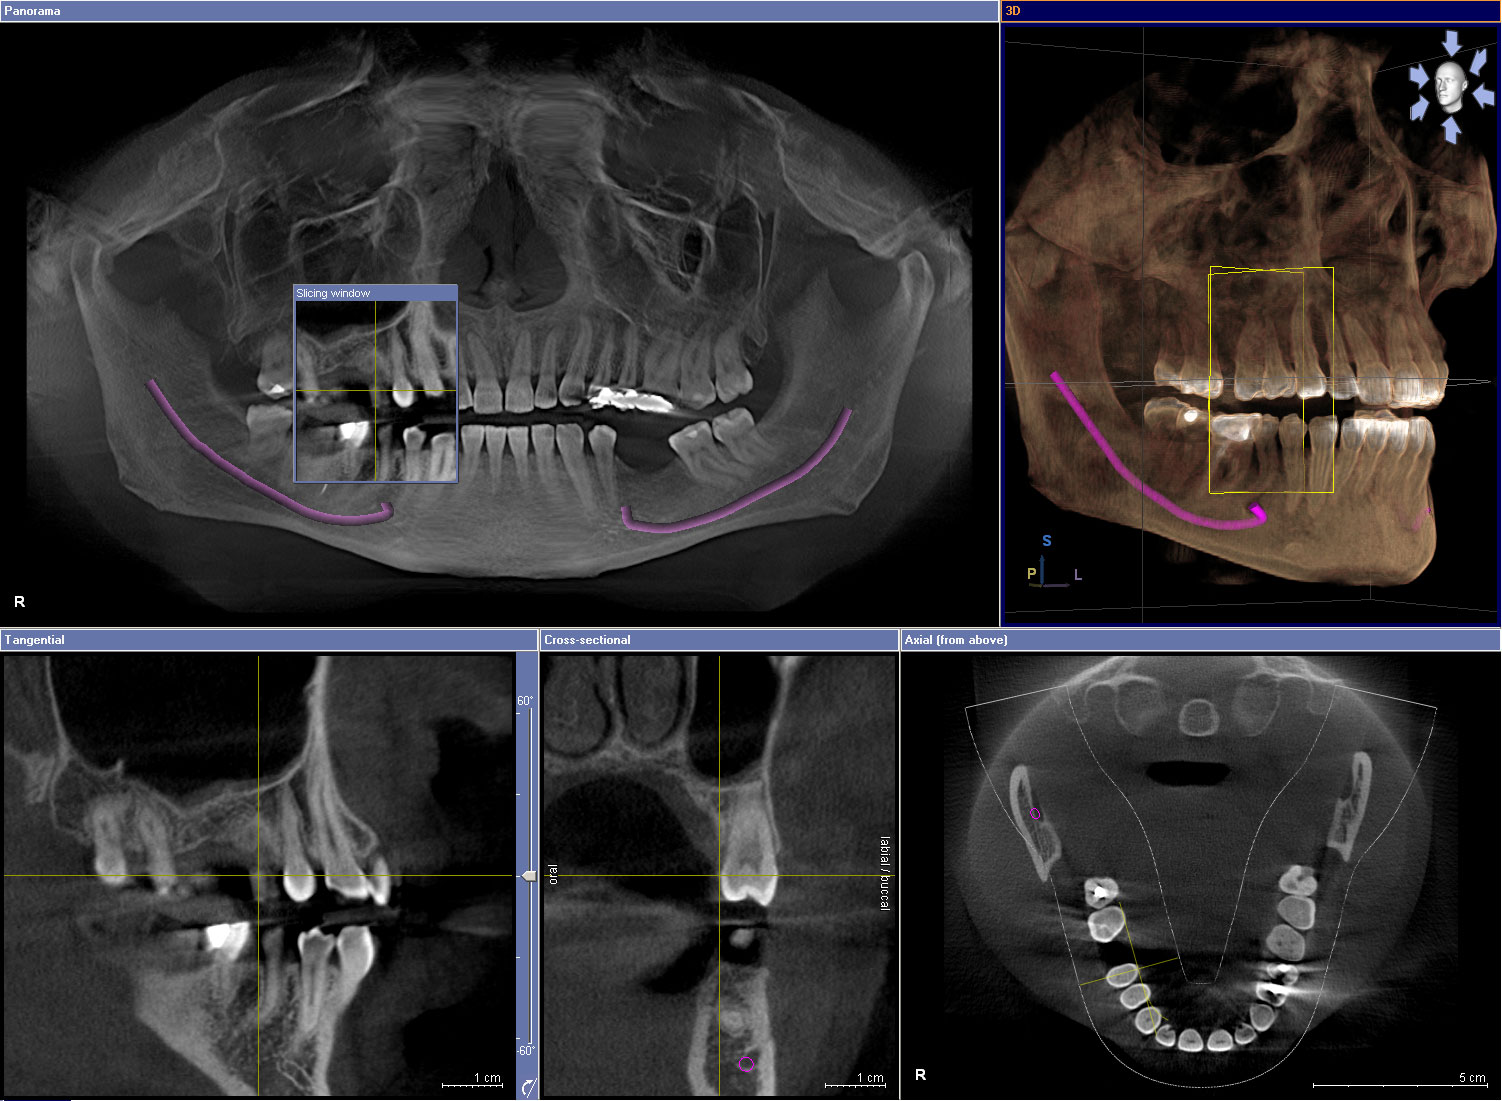

Oral surgery encompasses a range of procedures to address complex dental issues that cannot be resolved with routine treatments. Common oral surgery procedures include tooth extractions, wisdom tooth removal, bone grafting, and sinus lifts. Our surgical techniques prioritize patient comfort and optimal healing outcomes. Most procedures are performed in our office using local anesthesia and sedation options to ensure a comfortable experience.